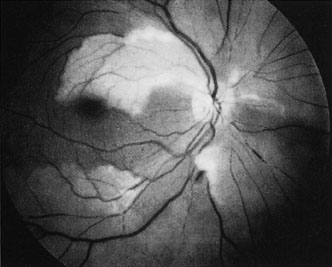

Obstruction of one of the posterior ciliary arteries may result in a whitening of the area of the retina supplied by the involved posterior ciliary artery and the subsequent appearance of patchy pigmentation in the same area. However, in patients with anterior ischemic optic neuropathy secondary to temporal arteritis the retina may appear normal (Fig. 5). In the case of either the medial posterior ciliary artery or the lateral posterior ciliary artery, the area involved is the size of approximately half of the choroid.121–123 In the case of a long posterior ciliary artery, the temporal side of the eye including the macula is involved.121

Fig. 5. A: Ischemic optic neuropathy in a patient with giant cell arteritis. B and C: Intravenous fluorescein angiography demonstrates delayed filling of the lateral posterior ciliary artery.

We have seen several patients with anterior ischemic optic neuropathy with suspected temporal arteritis where the Westergren sedimentation rate and C-reactive protein were normal and the intravenous fluorescein angiogram helped confirm the diagnosis (Fig. 5).